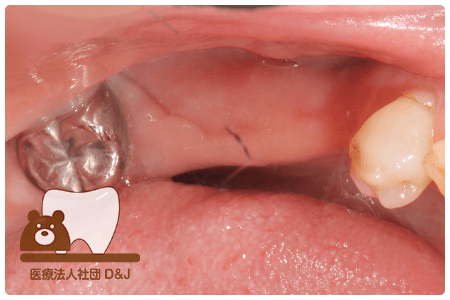

治療前

治療後

治療前

治療後

治療前

治療後

53歳 女性

- 治療内容

- 療内容奥歯にインプラントの埋入

- 治療期間

- 5ヶ月

- 費用

- 自費

インプラント体 1本:275,000円(税込)

インプラント上部構造(ジルコニア)2本:1本110,000円(税込)×2本=220,000円(税込)

(R8.3月時点)

- その他の治療の費用は含まれておりません。

- リスク・副作用

- インプラントは外科手術を伴うため、術後に腫れや痛み、出血、感染が生じることがあります。術後の指示を守らない場合、症状が悪化する恐れがあります。また、治療後に口腔内の清掃や定期的なメインテナンスを怠ると、インプラント周囲粘膜炎やインプラント周囲炎を引き起こすことがあり、インプラントの脱落につながる可能性があります。